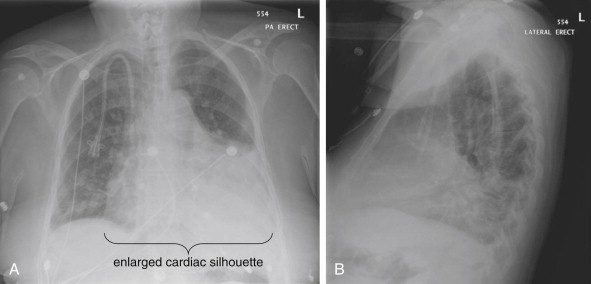

Frontal (Posterior–Anterior or Anterior–Posterior) Upright Chest X-ray View

The normal frontal upright chest x-ray (Figure 5-15 ) has the following features:

-

•

The cardiac silhouette occupies less than half of the transverse diameter of the thoracic cavity. The cardiac silhouette is crisp, with no adjacent pleural fluid or parenchymal opacities to disrupt the normal silhouette. The mediastinal width is less than 8 cm, and the aortic knob is well defined. The normal appearance of the aorta is described in detail in Chapters 6 and 7Chapter 6Chapter 7.